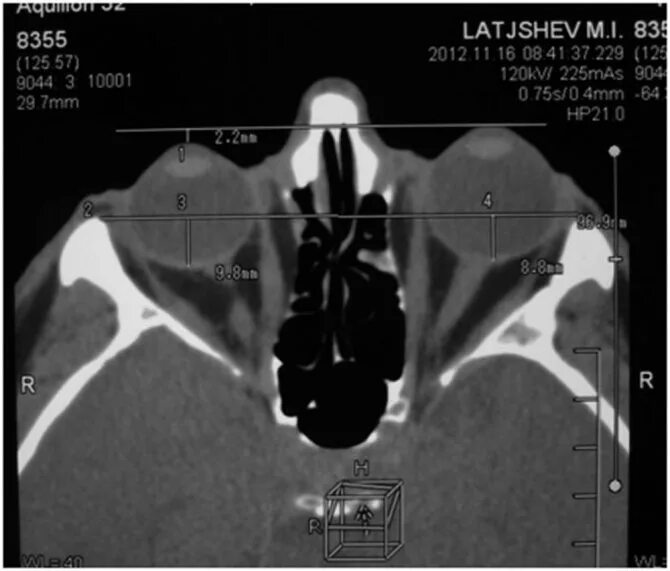

Костная ложа